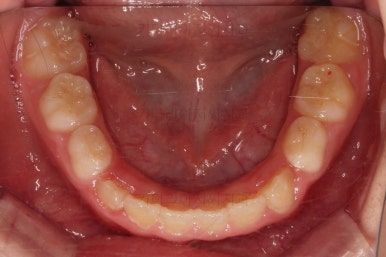

초진 시 입안의 모습입니다.

아래쪽 치열이 전반적으로 윗니보다 앞쪽에 위치한 전형적인 앵글씨 3급 부정교합인데요.

어금니에서부터 앞니까지 아랫니가 윗니보다 앞쪽에 위치하네요.

특히 앞니는 아랫니가 윗니보다 나와있는 "반대교합" 상태였고요.

또한 위아래로 겹침이 없고 떠있는 "개방교합" 상태였어요.

즉, 앵글씨 3급 부정교합 - 반대교합 - 개방교합 등 굉장히 복합적인 교합의 문제를 가진 환자였습니다.